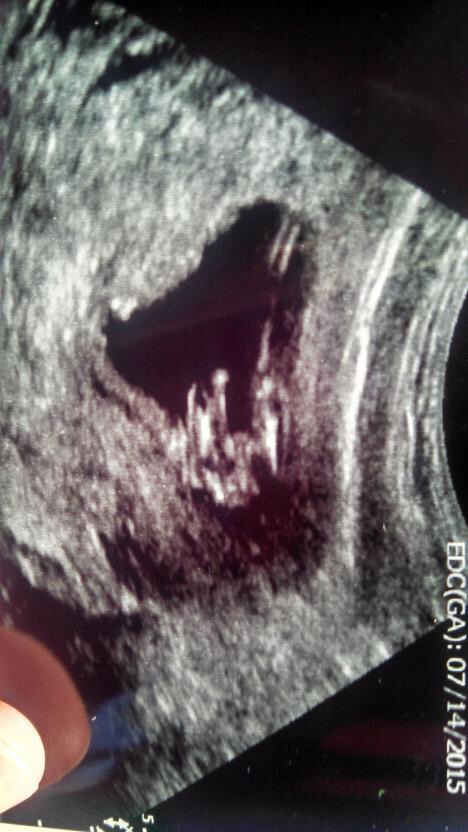

I also have a potty shot Attachment 22845

looking boyish but its a bit distorted. Potty shots all look the same at 12 weeks.

Do you have any other pictures? Potty shots are no good at this gestation